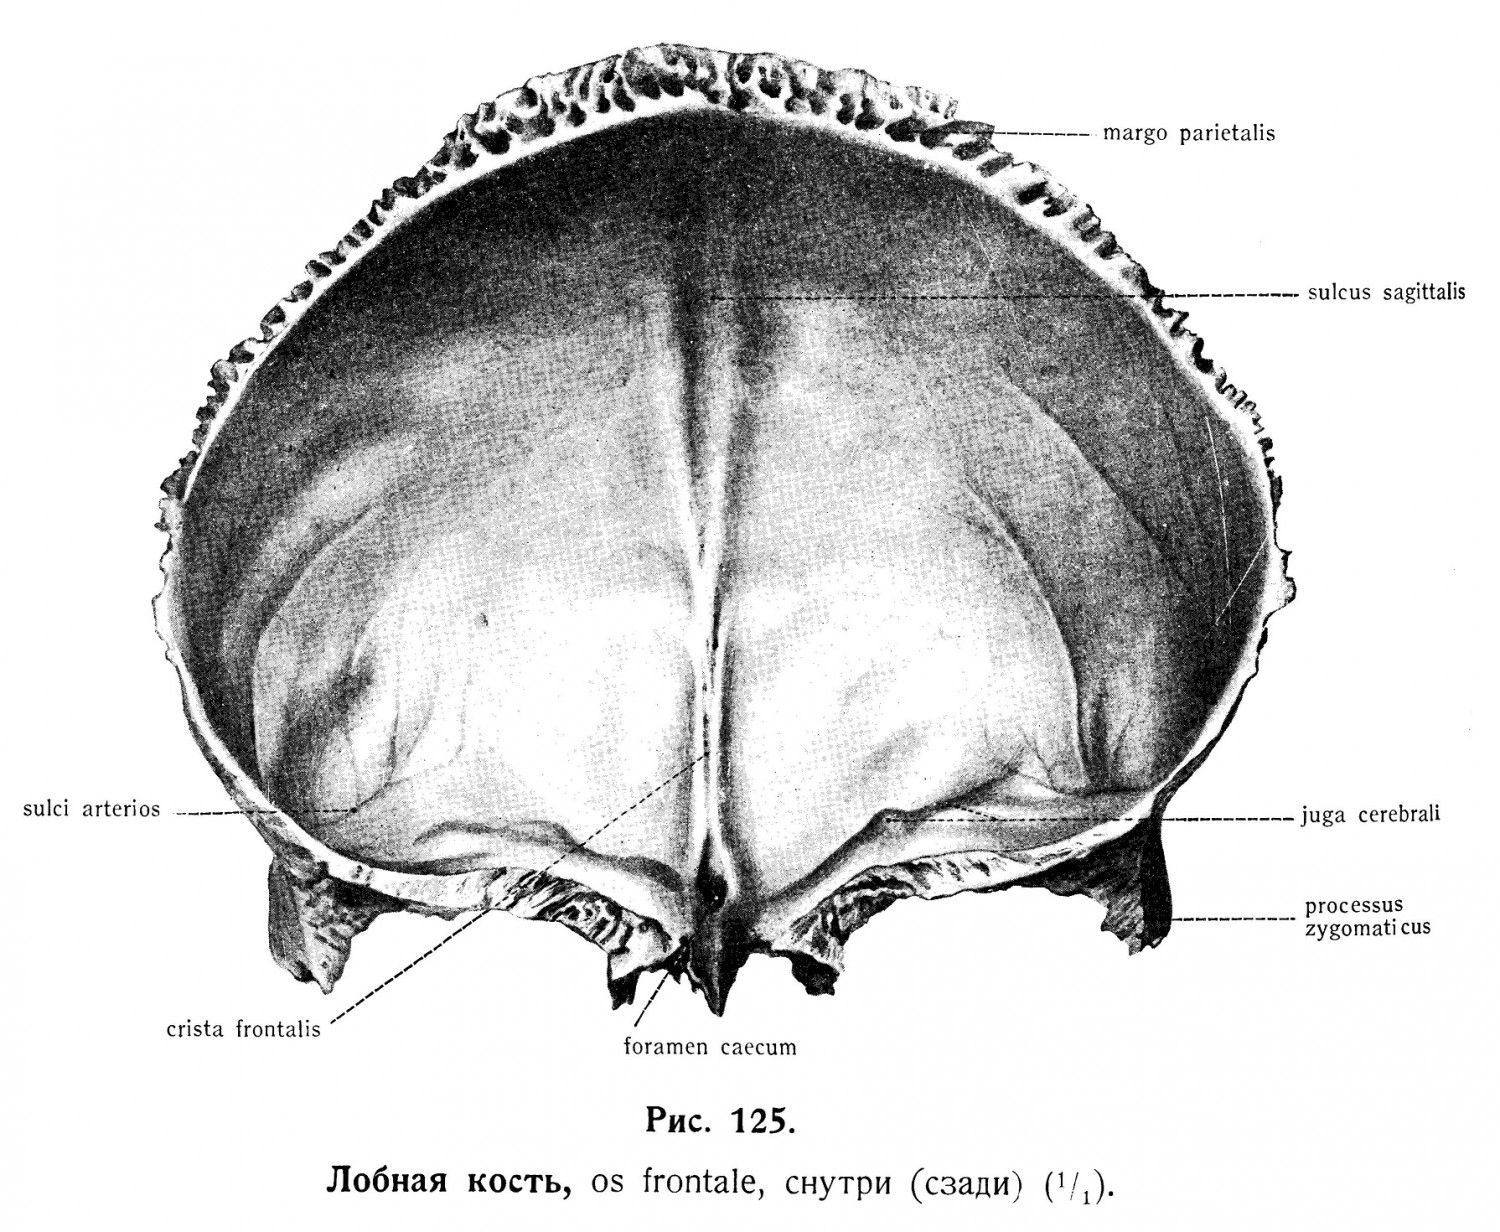

Анатомические изображения срединной сагиттальной линии черепа